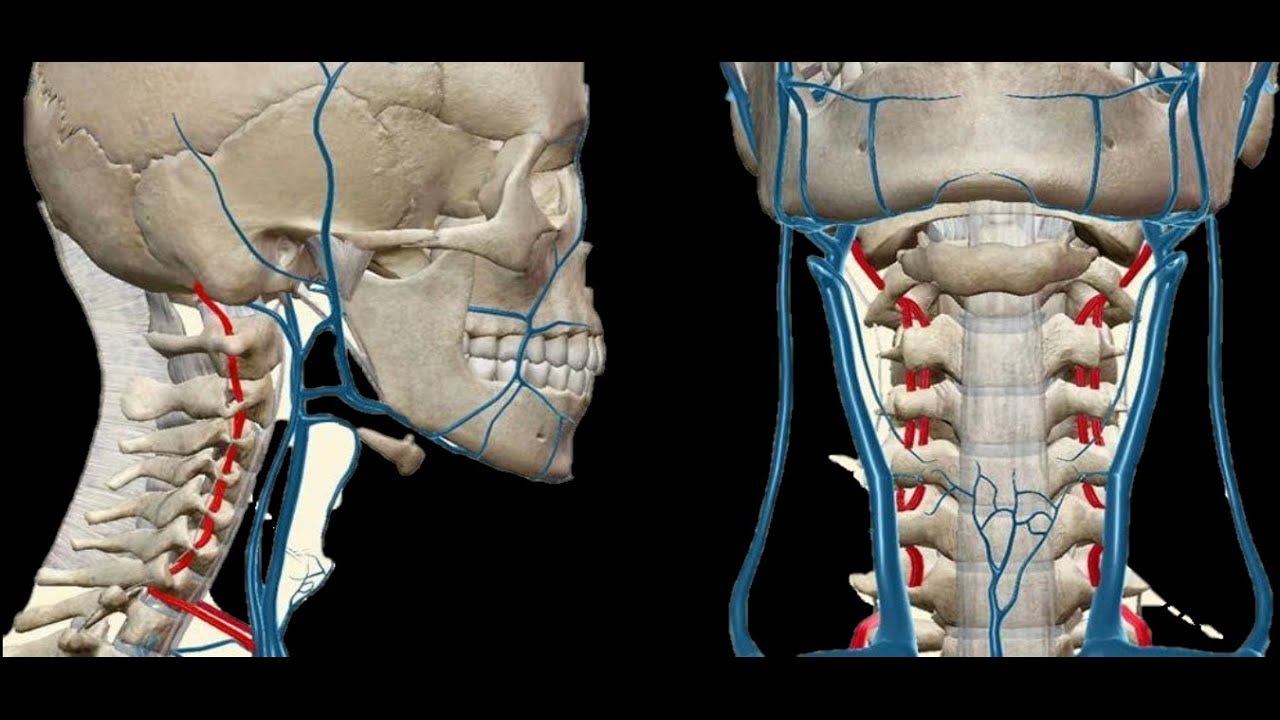

Грыжа в шее форум